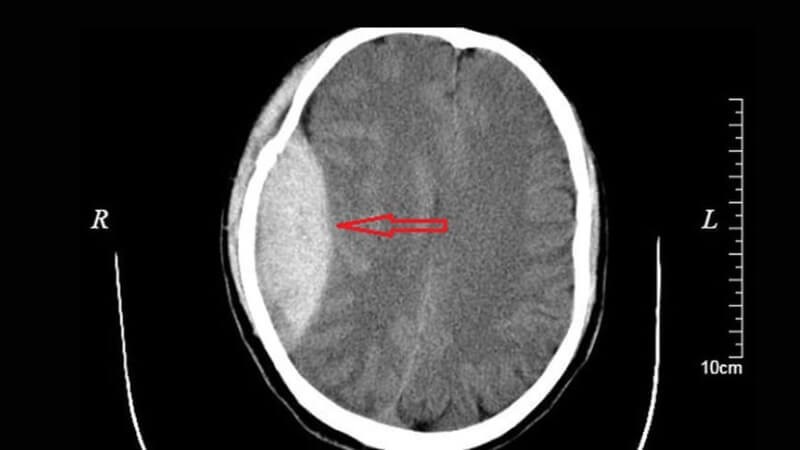

Bác sĩ có thể yêu cầu người bệnh chụp cắt lớp vi tính (CT scan) hoặc chụp cộng hưởng từ (MRI). Các xét nghiệm hình ảnh này giúp bác sĩ quan sát được hình ảnh não người bệnh, thấy được vị trí cũng như lượng máu đang chảy.[1]

Chụp cắt lớp vi tính giúp bác sĩ quan sát vị trí máu chảy trong não